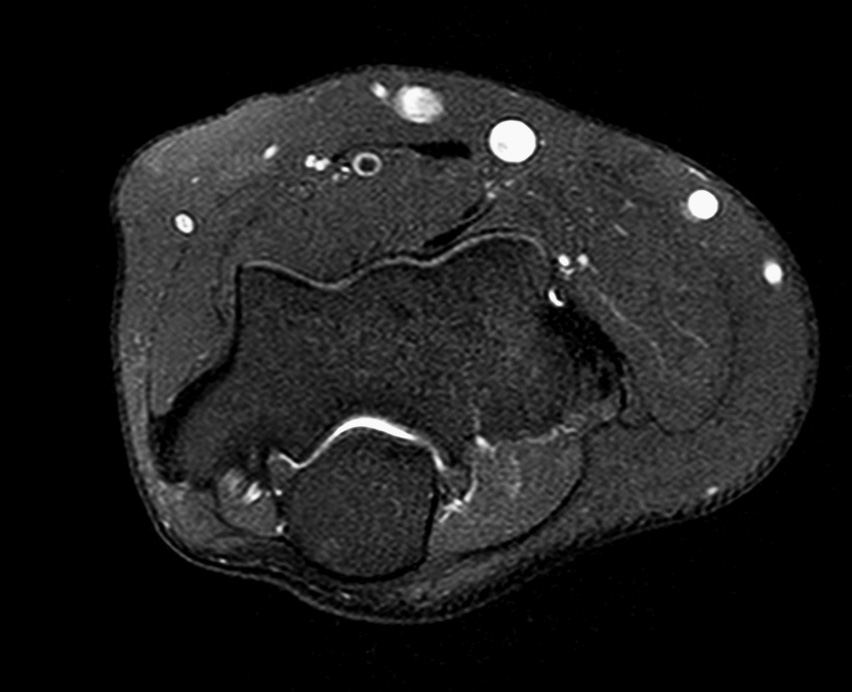

Elbow Imaging